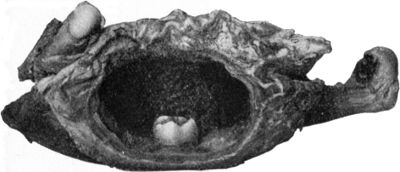

| 252. | Dentigerous Cyst of Mandible containing Rudimentary Tooth | 517 |

| 253. | Osseous Shell of Myeloma of Mandible | 518 |